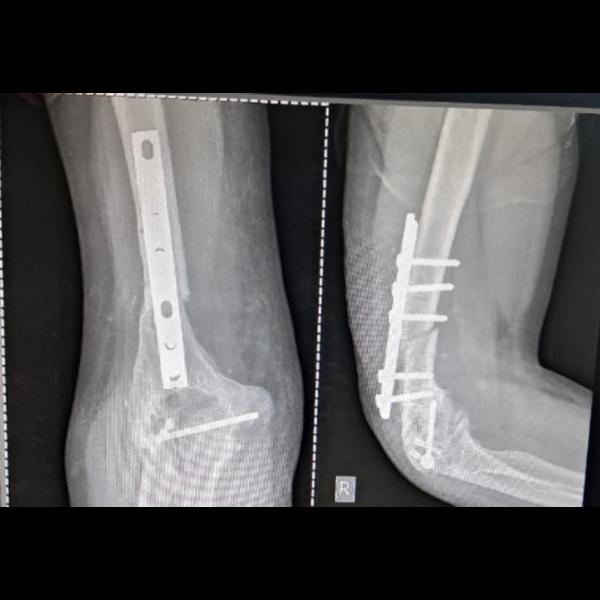

Non union of distal femur intraarticular fracture with implant failure operated elsewhere !